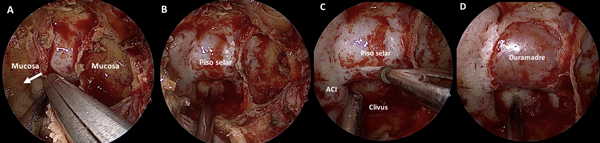

Se procede a la apertura del rostrum esfenoidal, la cual debe ser siempre amplia. Muchas veces es esto lo que proporciona un adecuado surgical freedom y no la amputación de estructuras nasales. Luego, se resecan todos los septos intrasinusales y se exentera la mucosa a fines de exponer con claridad todos los reparos anatómicos: la prominencia del piso de la silla turca al centro, la silueta de ambas arterias carótidas internas a los lados, el planum esfeno-etmoidal arriba y el clivus abajo (Figura 4 A-B).

Figura 4. Tiempo intrasinusal. A-D: exposición de la duramadre selar.

En este momento de la cirugía se suma un cirujano más; entonces uno de ellos maneja el endoscopio dinámicamente y otro el instrumental con ambas manos utilizando “1 y ½ fosa nasal” (i.e. 3-4 hands technique)12. El endoscopio es sostenido por un cirujano asistente en la fosa nasal derecha, hacia arriba (a horas 12.00). El cirujano principal sostiene un instrumento con cada mano: con la mano izquierda generalmente un cánula de aspiración de Frank-Pasquini que ingresa por la fosa nasal derecha sin entrar en conflicto con la óptica (a horas 06.00), y con la mano derecha el instrumento principal que va cambiando según el momento (e.g. bisturí, curetas, entre otros).13

En la fase selar la pared posterior del seno esfenoidal (i.e la prominencia selar) es fresada con punta diamantada a fines de disminuir su espesor (Figura 4C). Luego, se realiza una apertura “a medida” utilizando una pinza de Kerrison N°1. El plano dural queda expuesto hasta evidenciarse los “cuatro azules” o la “corona azul” (i.e. el limite más medial de ambos senos cavernosos y el límite de ambos senos intercavernosos)14 (Figura 4D).